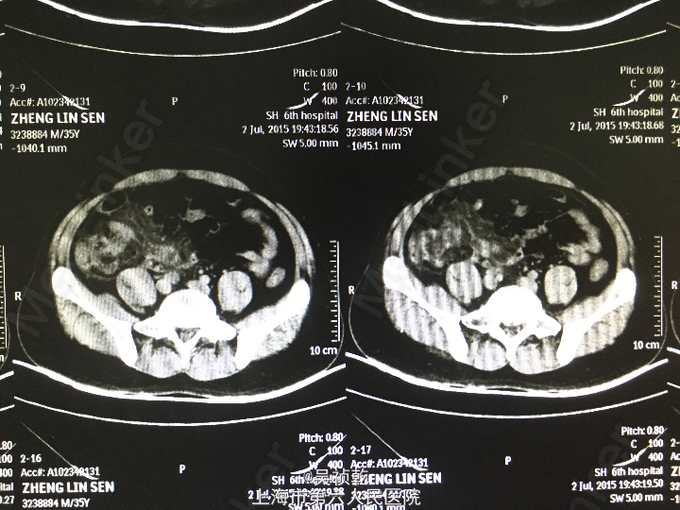

患者男性,35岁。因“右下腹疼痛1天,伴恶心、呕吐”入院。患者1个月前无明显诱因下脐周疼痛,后转移至右下腹,疼痛固定。无恶心呕吐,无头晕乏力。于外院拟尿路感染治疗,补液消炎1周后症状缓解。昨日下午,右下腹疼痛加剧,伴发热,体温约38.2摄氏度,有恶心,呕吐症状。故来我院治疗,完善各项检查,查腹部CT;阑尾形态增粗伴阑尾壁肿胀,回盲部及阑尾周围可见大量渗出,前列腺密度均匀,未见明显增大,两侧精囊未见明显异常,膀胱充盈可,盆腔未见明显肿大淋巴结,盆腔未见明显积液,。为进一步治疗收住入院。患者自起病以来,精神可,胃纳差,大便如常,小便如常,体重未见明显下降,睡眠一般。

查体:腹部平坦,无胃肠型。腹壁柔软,有压痛,位于右下腹,伴反跳痛,无腹部包块,振水音阴性,未触及肝;未触及脾 ,无移动性浊音,肝区无叩痛。肠鸣音正常。结肠充气试验:阴性;腰大肌试验:阴性;闭孔内肌试验:阴性。 辅查:2015-7-3 生化检验报告:血清钠(干式) 136 mmol/L ↓,总蛋白(干式) 60 g/L ↓,白蛋白(干式) 32 g/L ↓,谷草转氨酶(干式) 14 U/L ↓,总胆红素(干式) 62 μmol/L ↑。 血常规检验报告:白细胞 14.3 X10^9/L ↑,红细胞 5.18 X10^12/L ,淋巴细胞百分比 9.5 % ↓,嗜酸性细胞百分比 0.1 % ↓,中性细胞百分比 84.8 % ↑,嗜酸性细胞绝对值 0.01 X10^9L ↓,单核细胞绝对值 0.8 X10^9L ↑,中性细胞绝对值 12.1 X10^9L 腹部CT:阑尾形态增粗伴阑尾壁肿胀,回盲部及阑尾周围可见大量渗出,前列腺密度均匀,未见明显增大,两侧精囊未见明显异常,膀胱充盈可,盆腔未见明显肿大淋巴结,盆腔未见明显积液,。